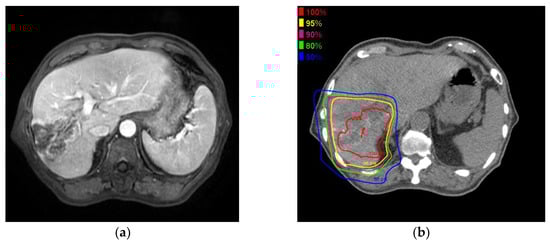

Figure 2 shows the MRI and PBT planning results of a successfully treated 64-year-old man with a large HCC in the right hepatic lobe (Figure 2a). He was treated with PBT at 80 GCE in 25 fractions (Figure 2b,c). The tumor shrank and was controlled 2 years after PBT (Figure 2d). He showed no severe complications during a 2-year follow-up.

Figure 2.

A 6.3 cm hepatocellular carcinoma (HCC) was treated by proton beam therapy (PBT) in a patient with Child–Pugh class A liver disease and right portal vein tumor thrombosis. (a) Early enhancement of the HCC was shown in the arterial phase of gadolinium ethoxybenzyl diethylenetriamine pentaacetic acid-enhanced dynamic magnetic resonance imaging (Gd-EOB-MRI); (b) The isodose lines were shown on planning CT (axial view); (c) This tumor was close to the colon (coronal view); (d) HCC was shown in the arterial phase of EOB-MRI 2 years after PBT.